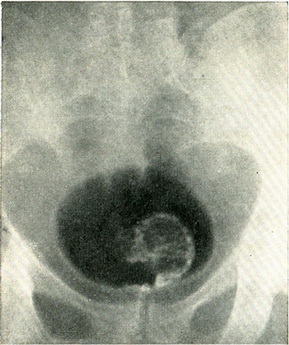

Гістологічне дослідження шматочка пухлини, взятого гострою ложечкою через цистоскоп, дозволяє диференціювати пухлину із грануляційною тканиною, туберкульозом або іншими запальними процесами. За даними біопсії далеко не завжди вдається встановити доброякісність або злоякісність пухлини. При цистографії з 10% розчином сергозина на місці пухлини видно дефект наповнення. Якщо контури міхура залишаються при цьому незмінними, то пухлина з великою ймовірністю можна вважати неинфильтрирующей (рис. 111). Якщо поряд з дефектом наповнення нерівні контури міхура, є асиметрія менаду правою і лівою половиною міхура, то в инфильтрирующем характер пухлини можна не сумніватися (рис. 112).

Цистографія з сірчанокислим барієм (осадова цистографія) демонструє локалізацію і розмір пухлин. В міхур, звільнений від сечі, вводять 10% суспензії сірчанокислого барію. Через 30 хвилин хворий мочиться, і в міхур вводять 100-150 см3 кисню. Частинки барію осідають на ворсинках пухлини, і на знімку чітко видно її розміри і форма (рис. 113).

![]() Рис. 113. Папілярна пухлина сечового міхура. Цистограмма з 10% суспензією сірчанокислого барію і подальшим наповненням міхура киснем (осадова цистограмма). |